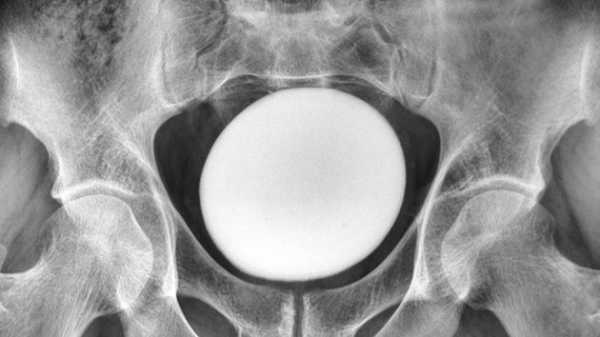

The diagnosis: Afterward, the medical staff examined the patient’s soft tissue via CT scanning. From these scans, they spotted a deposit of trapped nitrogen gas within the patient’s abdominal area, just above his stomach and beneath his lungs — a state known as pneumoperitoneum. This verified that the gas had ruptured the man’s stomach and gathered on top of it.